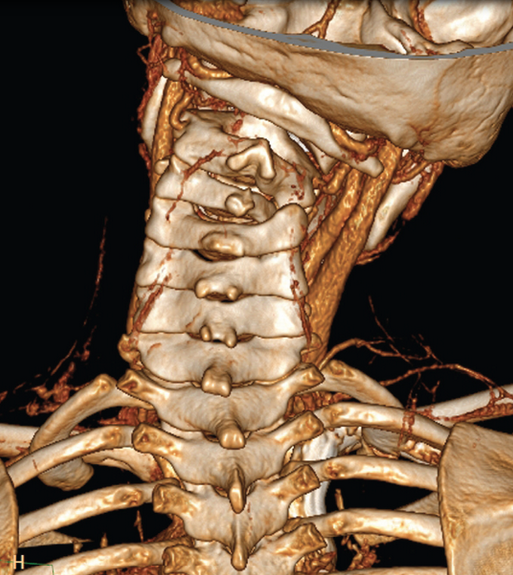

An MRI scan confirmed a unilateral facet dislocation without ligamentous disruption or cord compression. A neurosurgeon evaluated the child, who was admitted to the pediatric ICU for cervical traction and cervical collar placement. He was discharged 3 days later in stable condition. Although no history of trauma was initially given, the mother later stated that the boy wrestled with his brother nearly every day and may have injured his neck at the time of initial presentation. One month later, the child underwent C3-4 diskectomy with anterior fusion of C3-4. At that time he was noted to have congenital absence of the C4 pedicle (Figure 3). He was discharged 2 days after the operation and had no complications.

The absence of a cervical pedicle is a rare congenital anomaly often misdiagnosed as a jumped facet on initial imaging. Patients typically present with pain and spasm after minor trauma, and this may be merely an incidental finding. Misdiagnosis may lead to unnecessary surgical intervention because conservative management is often sufficient.

Figure 3 – A 3-dimensional reconstruction demonstrates the congenital absence of the

left-sided C4 pedicle.